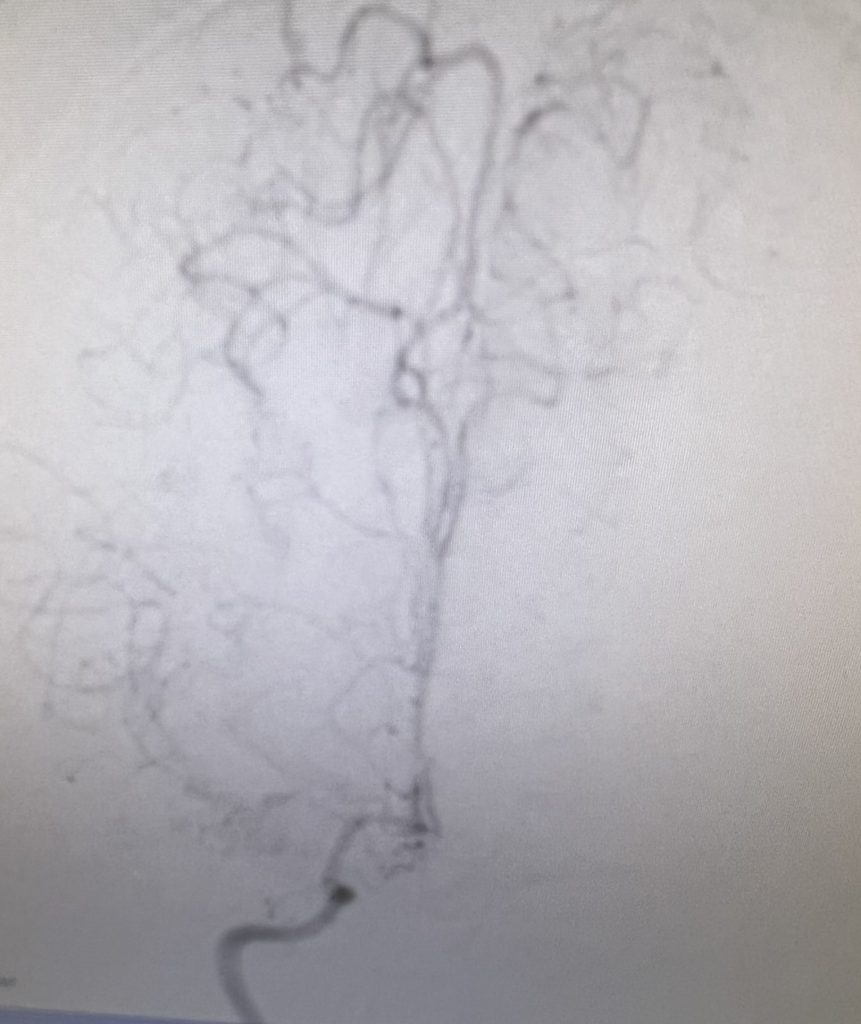

Figure 3

A right sided Encephaloduroarteriosynagios (EDAS) procedure was undertaken in which the right superficial temporal artery (STA) is sewn (synangiosed) to the pia in an effort to generate vascular arborization and increased blood flow to the hemisphere (Figure 3).